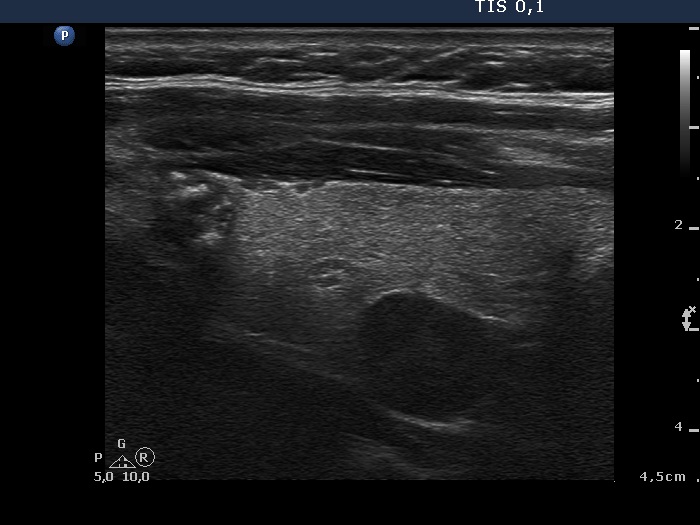

Benign colloid goiter (cytological diagnosis)

This nodule presents different types of hyperechogenic granules, the ventral figures are either comet-tail artifacts or punctate echogenic foci, while although the primary focus cannot be seen, the acoustic shadows prove that there are coarse calcifications, as well.